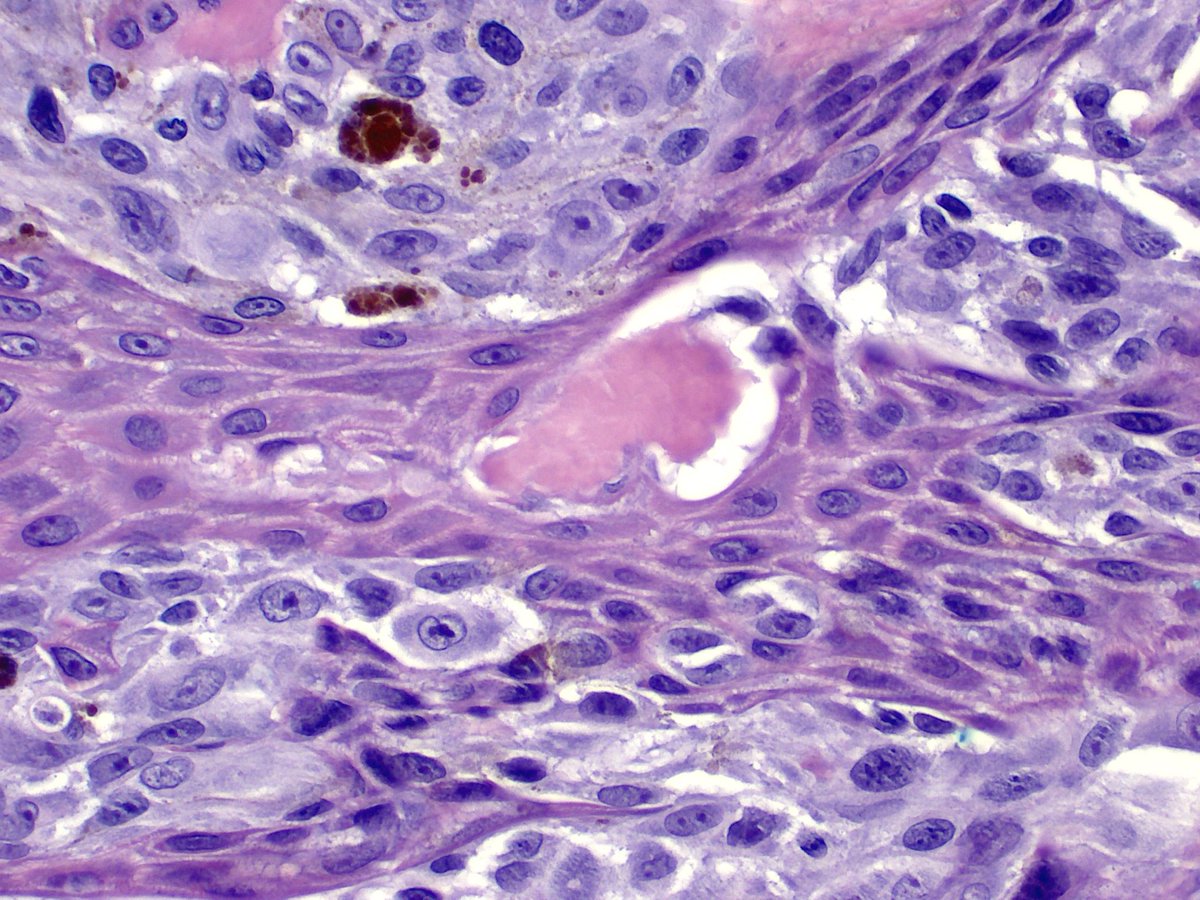

One typical feature of NTRK1 fusion Spitz lesions is a "nest of nests" pattern - what looks like a nest at low power turns out to be smaller nests rammed together at higher power. IHC is pan NTRK. #dermatology #dermpath #pathology